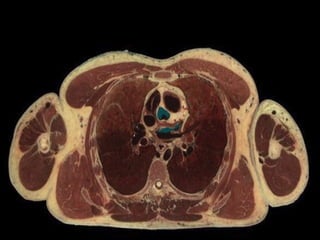

NODULO O MASA -ASINTOMATICO -INCIDENTAL

NODULO O MASA-ASINTOMATICO -INCIDENTAL